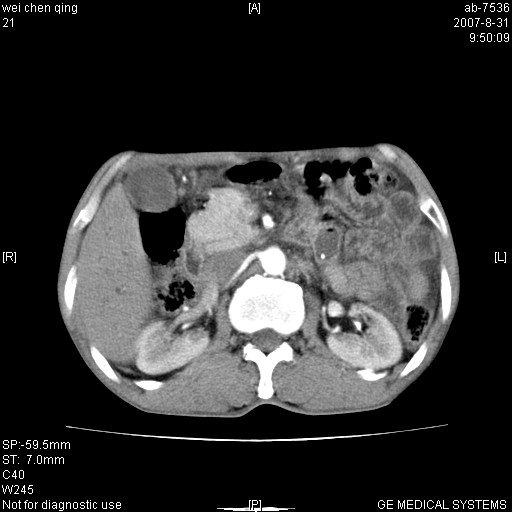

以下是引用zyyzzy在2007-8-31 14:34:00的发言:[br]该病人肝内胆管扩张,胆囊及胆总管未见明显扩张。在倒数第9层图像上可看到左右肝管结合部(肝总管)有软组织影,此处应薄层扫描。考虑肝总管占位(ca)、腹水。[br]